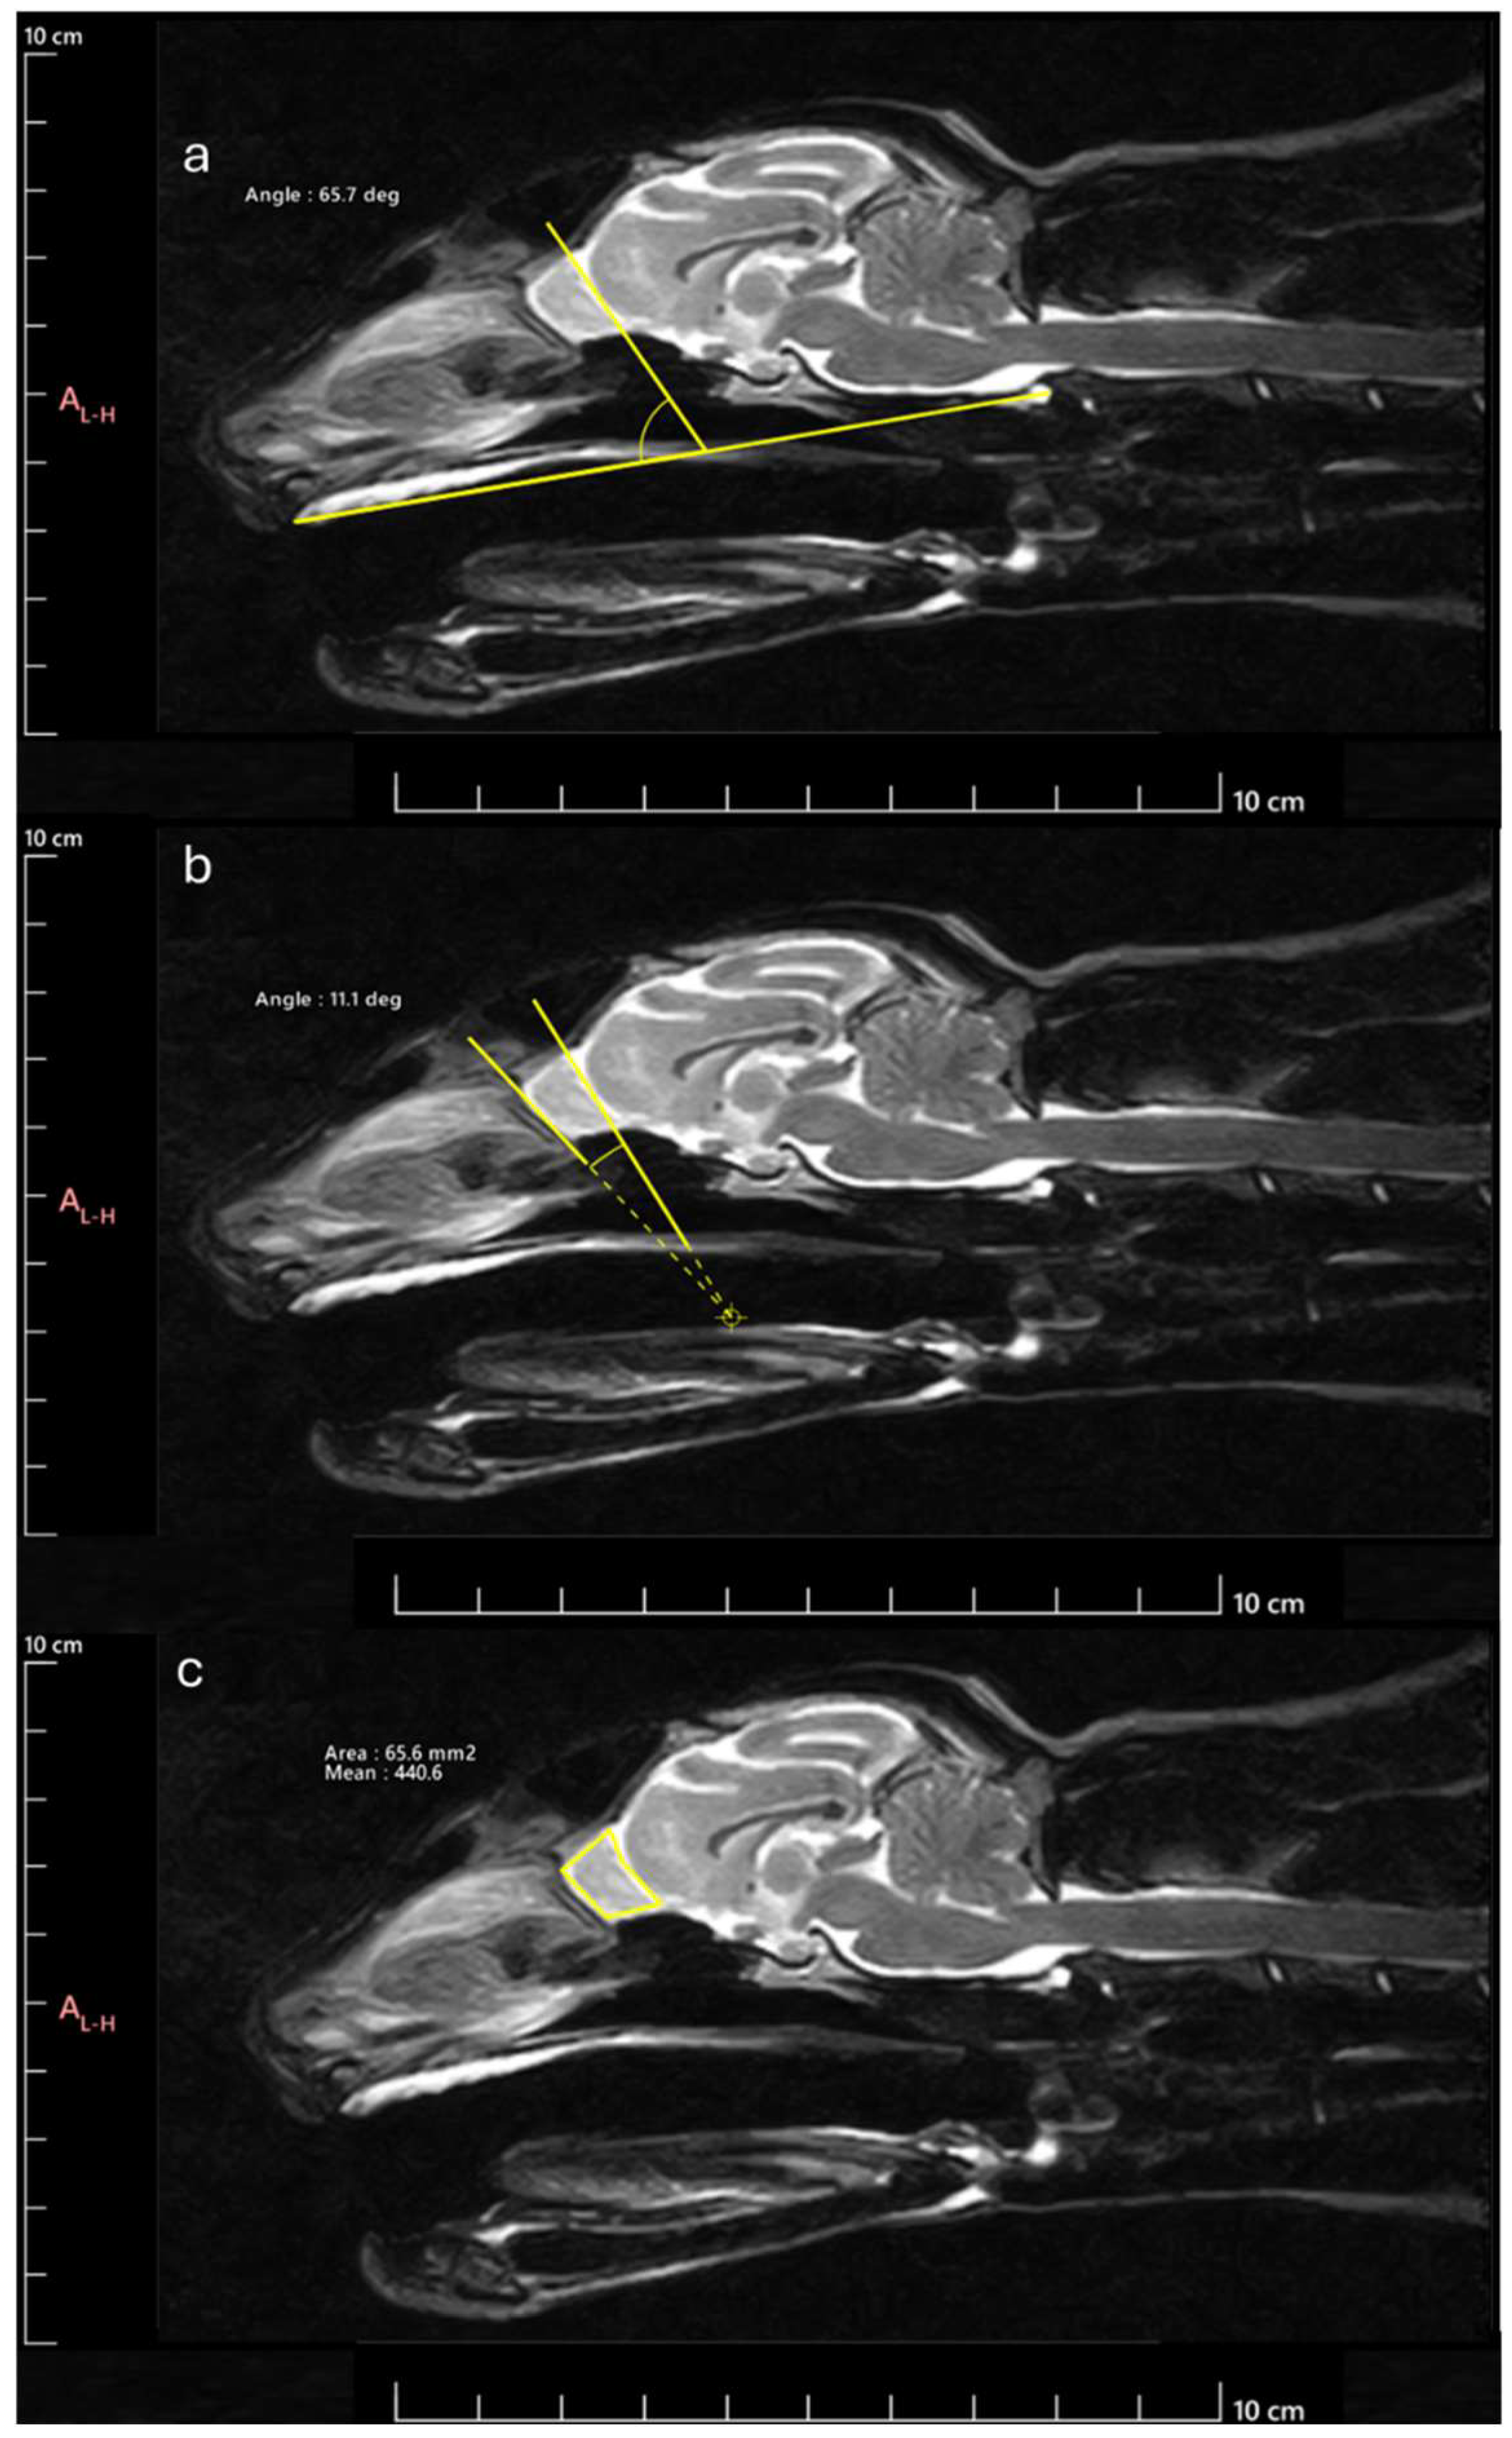

Figure 2. Methodology for determining the parameters considered: a) OBA: angle formed by the line passing through the olfactory fissure and the line between the hard palate and the intercondylar notch of the foramen magnum; b) OBO: open angle formed by the lines that pass through the olfactory fissure and the most rostral limit of the OB; c) OBSA: automatically determined using the polygonal selection tool.

Next, the OB was measured to determine the following parameters: OB angle (OBA), OB orientation (OBO), and OB sagittal section area (OBSA). The OBA was calculated applying the methodology described by [17]. Briefly, the angle formed by the line passing through the olfactory fissure and the line between the hard palate and the intercondylar notch of the foramen magnum was determined (Figure 2a). The OBO was evaluated considering the open angle formed by the lines that pass through the olfactory fissure and through the most rostral limit of the OB (Figure 2b). Bigger angles were considered to correspond to OB with dorsal orientation and smaller angles to OB with ventral orientation. The OBSA was determined automatically using the polygonal selection tool of the selected software (Figure 2c), a tool that allows to draw custom polygonal shapes over the MRI images to delineate regions of interest and to precisely measure variables such as area after defining the vertices of the desired polygon, in this case, the limits of the OB in sagittal section. The same image reviewer carried out three measurements of all variables in all images on different days, with the average of the three measurements being considered in all cases. Whenever differences greater than 10% were observed between measurements of the same variable in the same animal, a new measurement was taken, and the 3 closest values were considered for the final average.